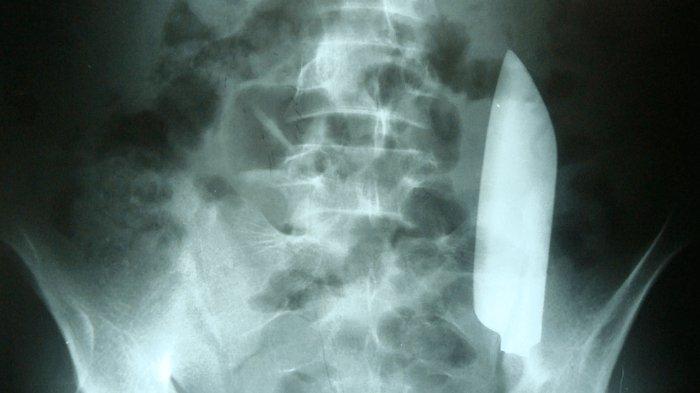

Hasil rontgen memperlihatkan sebilah pisau berukuran 6 inci yang menancap di perutnya.

Setelah dilakukan rontgen, dokter kemudian menemukan sebuah pisau besar yang ada di dalam perutnya.

Pisau itu melayang melintasi perut dari sisi kanan ke kiri.

Meski melintang di dalam tubuh, pisau itu tampaknya tidak melukai organ dalam lainnya, menurut laporan kasus di jurnal Cureus.